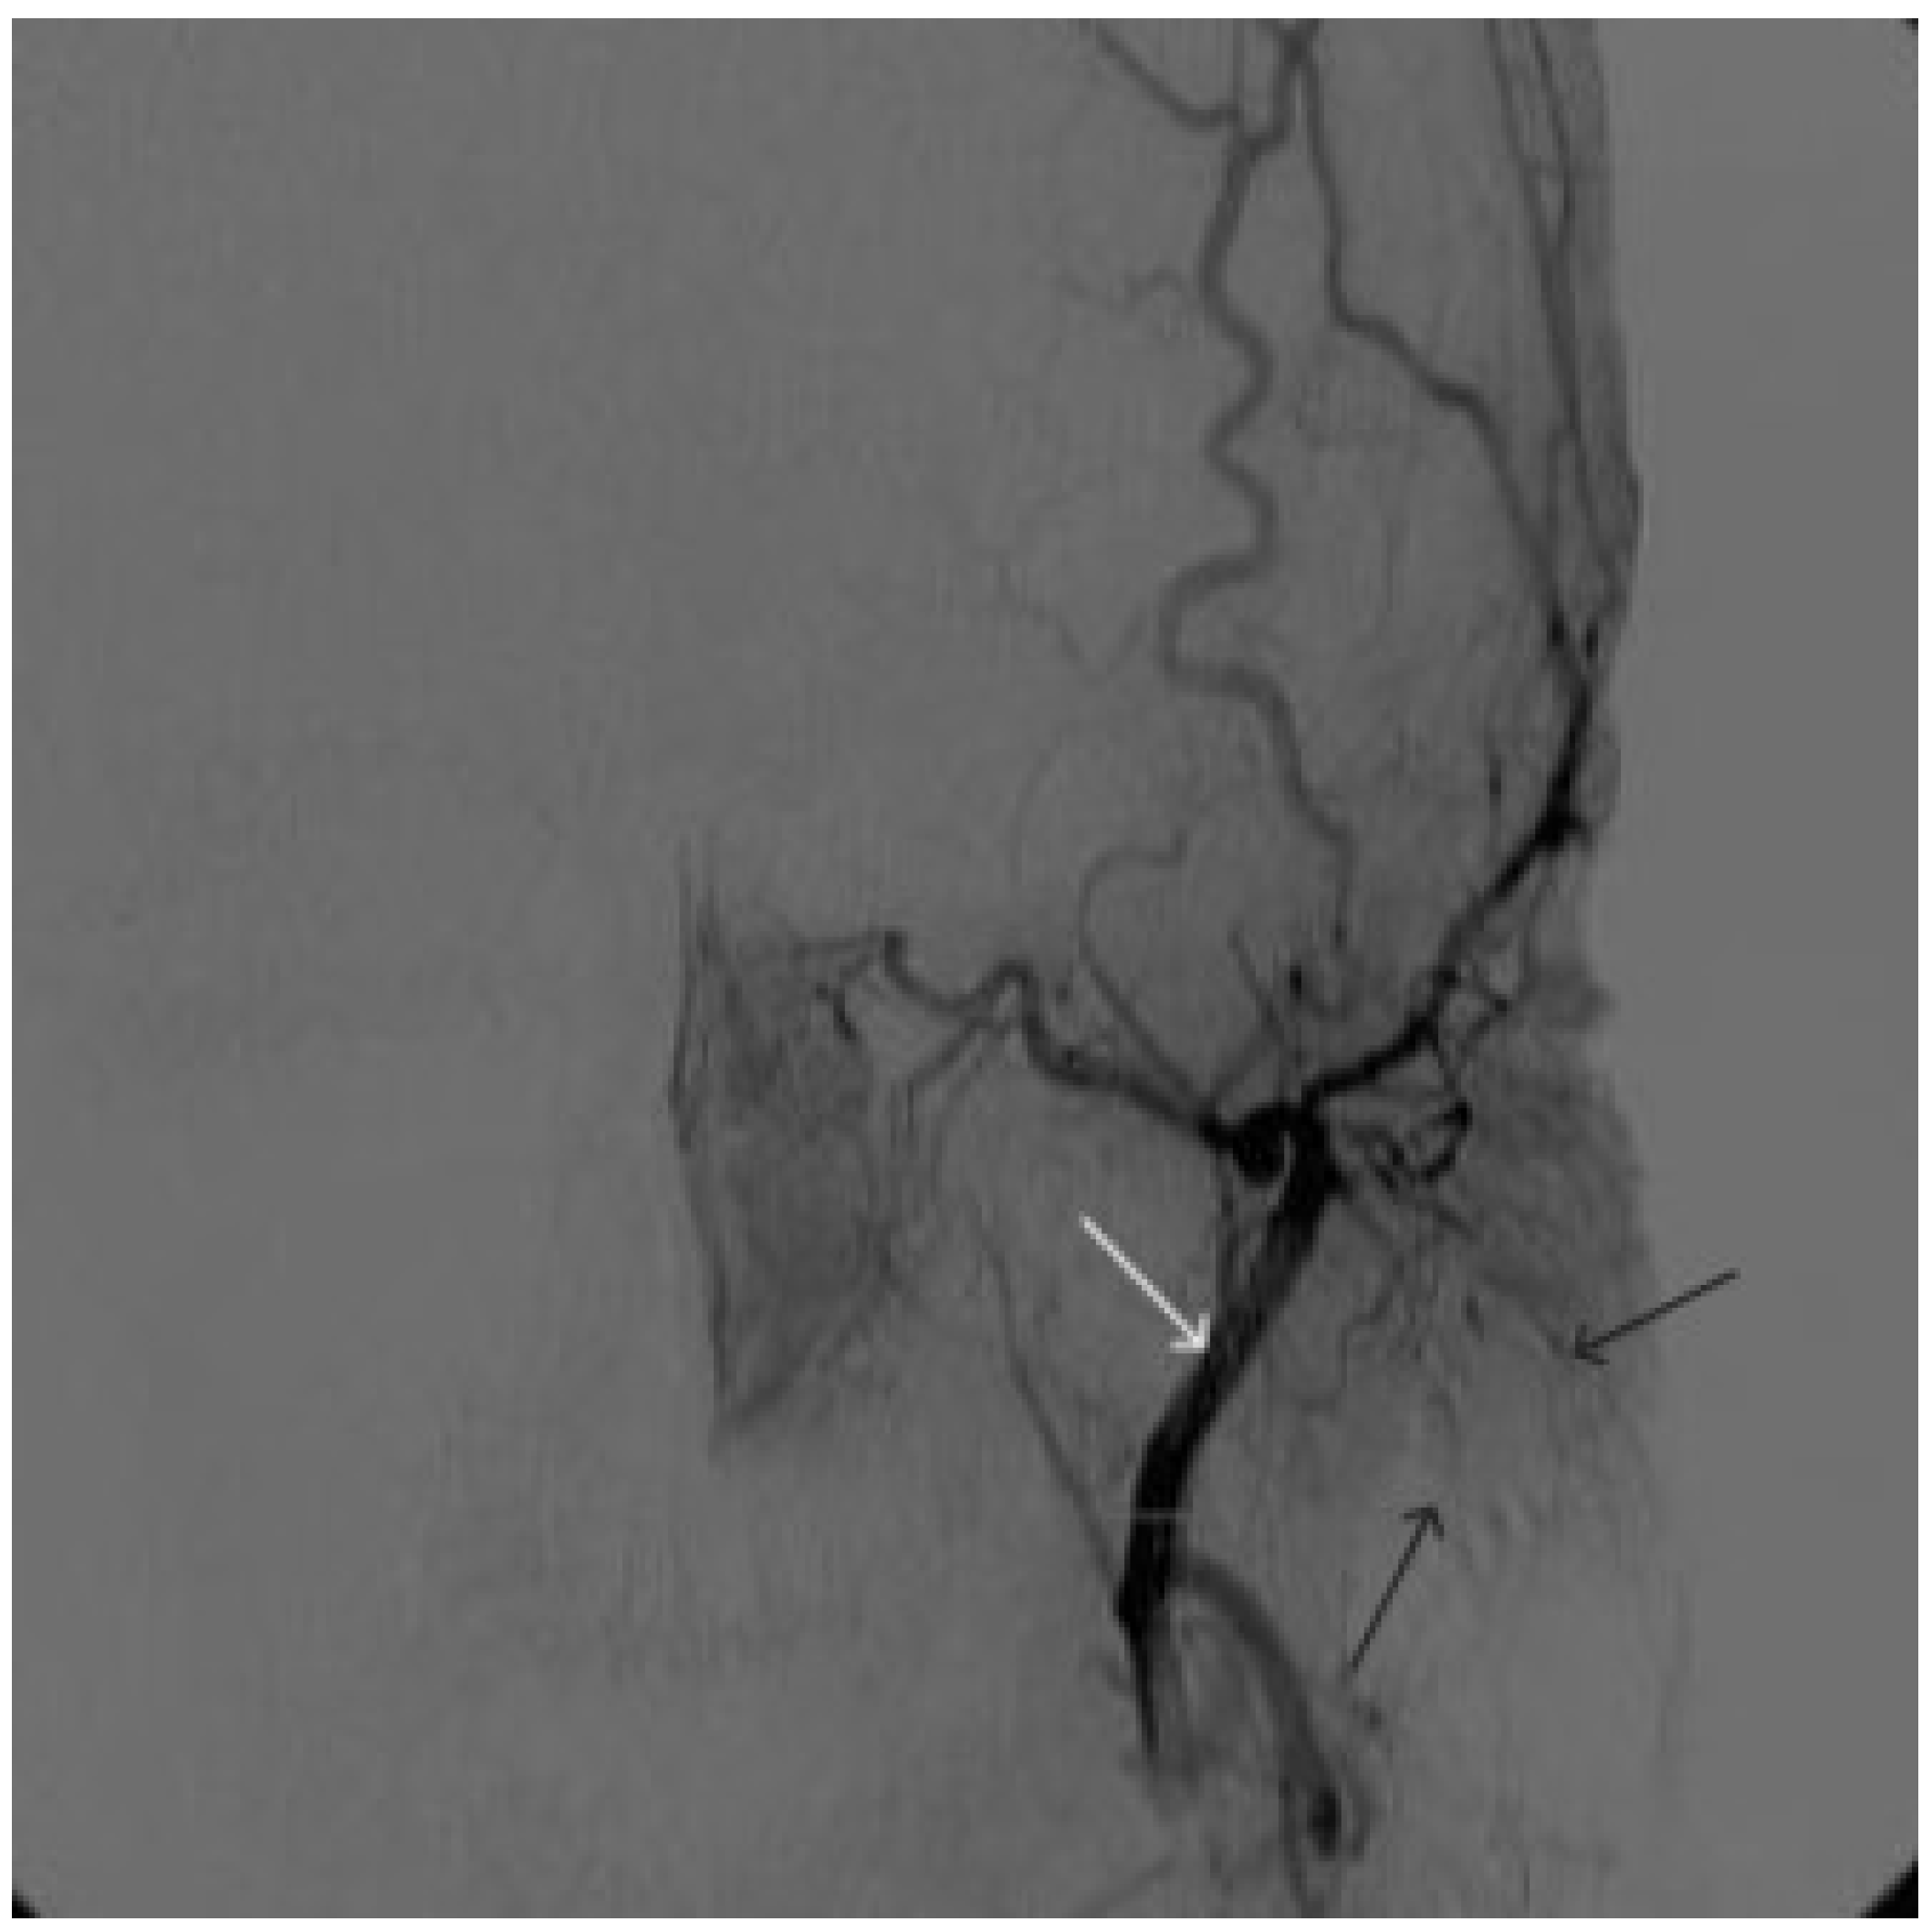

Figure 14. Digital subtraction angiography from the left common carotid artery: a – direct projection, b - lateral projection (white arrows indicate the guiding catheter in the left external carotid artery, black arrows indicate the boundaries of the embolized paraganglioma).